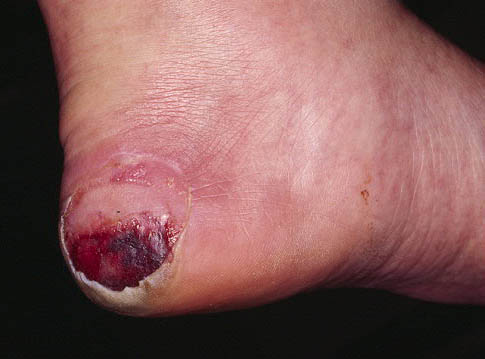

UPP de 3º-4º en talón.